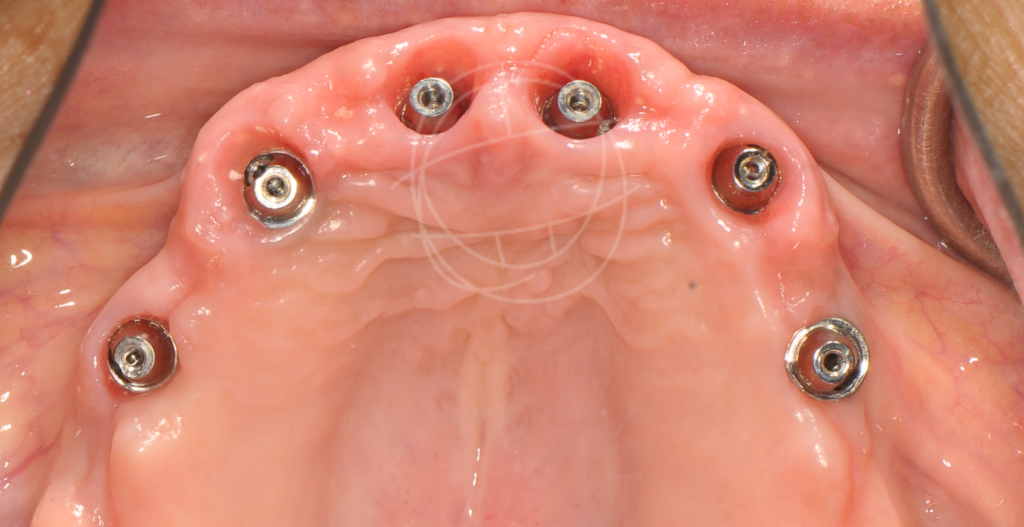

Τα οδοντικά εμφυτεύματα έχουν μεταμορφώσει τη σύγχρονη οδοντιατρική από την ανακάλυψη της οστεοενσωμάτωσης από τον Per-Ingvar Brånemark το 1952, της διαδικασίας όπου το τιτάνιο συντήκεται φυσικά με το οστό. Αυτή η ανακάλυψη οδήγησε στα πρώτα επιτυχημένα εμφυτεύματα τιτανίου το 1965, αποδεικνύοντας τη μακροπρόθεσμη σταθερότητα και ασφάλειά τους. Σήμερα, τα οστεοενσωματωμένα οδοντικά εμφυτεύματα τιτανίου αποτελούν μια αξιόπιστη, ευρέως χρησιμοποιούμενη λύση για την αποκατάσταση ελλειπουσών δοντιών και τη θεραπεία σύνθετων στοματικών παθήσεων.

Ένα οδοντικό εμφύτευμα είναι μια «τεχνητή ρίζα» από βιοσυμβατό τιτάνιο, που τοποθετείται χειρουργικά στο οστό της γνάθου. Πάνω του στηρίζεται μια στεφάνη (το «τεχνητό δόντι»), η οποία μοιάζει και λειτουργεί όπως ένα φυσικό δόντι. Γι’ αυτό και συχνά τα εμφυτεύματα θα τα ακούσετε ως «βιδωτά» ή «φυτευτά» δόντια.

Η προσέγγιση που ακολουθούμε βασίζεται σε επιστημονικά πρωτόκολλα και εξατομικευμένο σχεδιασμό, ώστε κάθε ασθενής να έχει ένα φυσικό και μακροχρόνια επιτυχημένο αποτέλεσμα.